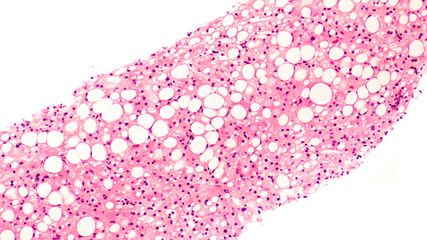

Die Arbeitsdiagnose einer MASLD (mit metabolischer Dysfunktion assoziierte steatotische Lebererkrankung – bis vor Kurzem als NAFLD bezeichnet) ist einfach: Wird mittels Bildgebung, in der Regel Ultraschall oder Biopsie, eine Steatose der Leber festgestellt und liegen kardiometabolische Risikofaktoren, jedoch kein hoher Alkoholkonsum vor, so kann von einer MASLD ausgegangen werden. Kommen Inflammation und möglicherweise Fibrose hinzu, so spricht man von MASH (mit metabolischer Dysfunktion assoziierte Steatohepatitis). Bei 80% der Betroffenen bleibt es bei einer Steatose mit allenfalls minimalem Progressionsrisiko, erläuterte Univ.-Prof. Dr. Herbert Tilg, Leiter der Innsbrucker Universitätsklinik für Innere Medizin I. In 20% der Fälle liegt jedoch eine MASH vor, die mit einem beträchtlichen Risiko für Progression zu Zirrhose und Dekompensation sowie mit einer erhöhten Inzidenz von Leberkarzinomen assoziiert ist. In dieser Patientengruppe ist die Mortalität signifikant erhöht, wobei kardiovaskuläre Todesursachen die größte Rolle spielen. Daher besteht erheblicher Bedarf an wirksamen Therapien, so Tilg, der ergänzte, dass man bis heute nicht vollständig verstehe, warum es bei der Mehrheit der Betroffenen bei MASLD bleibt, während ein Teil eine MASH entwickelt. Dabei dürften extrahepatische Signale, unter anderem aus dem Fettgewebe, aber auch bakterielle Stoffwechselprodukte aus dem Darmmikrobiom eine wichtige Rolle spielen.1

Man ging bei MASH bislang weitgehend von einer sterilen Entzündung der Leber aus, so Tilg. Allerdings wird aktuell intensiv diskutiert, ob nicht doch auch Bakterien in der Leber an der Genese einer MASH beteiligt sein könnten. Zumindest bakterielle DNA werde häufig in der Leber von MASH-Patienten gefunden. Ob auch ganze bzw. lebende Bakterien im Spiel sind, müsse noch geklärt werden. Tilg: „Möglicherweise wird das Dogma der sterilen Inflammation in Zukunft infrage gestellt.“ Ebenso sind Lipide involviert. Hepatisches freies Cholesterin treibt die Entzündung ebenso wie Sphingolipide. In präklinischen Modellen induziert auch Fruktose die Entwicklung von MASH, Fibrose und hepatozellulärem Karzinom (HCC) – klinische Daten sprechen für einen proinflammatorischen Effekt von Fruktose.2 Im Gegensatz dazu hat Gewichtsreduktion einen ausgeprägten antiinflammatorischen Effekt, der durch die Senkung der Spiegel von Interleukin 1β mediiert wird.3

In einer Phase-III-Studie mit knapp tausend Patienten wurde mit Resmetirom über 52 Wochen bei 25,9% der mit 80mg und bei 29,9% der mit 100mg behandelten Patienten eine Senkung des NAFLD-Activity-Scores (NAS) um mindestens zwei Punkte ohne Verschlechterung der Fibrose beobachtet (Abb. 1A). Bei 24,2% (80mg) und 25,9% (100mg) der Patienten konnte eine Reduktion der Fibrose ohne Verschlechterung des NAS erreicht werden (Abb. 1B). Resmetirom erwies sich im Vergleich zu Placebo als signifikant überlegen. Zusätzlich kam es in den Verumgruppen zu einer signifikanten Senkung des LDL-Cholesterins zu Woche 24 (Abb. 1C).7 Tilg: „Wir beginnen zu verstehen, welche Bedeutung die Schilddrüse für die Leber hat.“